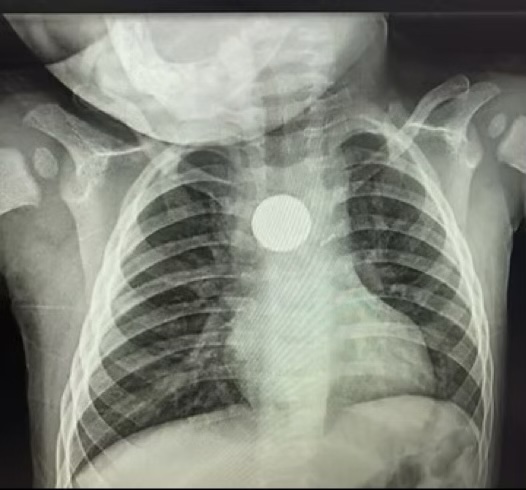

You may or may not heard of my son Ralphie’s story or the harper lee foundation, but I hope you have because it means we are saving lives like I promised myself one year ago as I handed over my son to a major trauma team of surgeons to save his life as he laid in my arms dying on his first birthday. As I sat waiting for him to survive and the 3 weeks we spent in hospital feeding him through a tube and watching machines keep him alive for the second time in his life I knew this could never happen again, I could not allowed anymore families to experience this when so many people don’t know that one little thing every household has in so many things could potentially kill or seriously injure their children or pets.

This is important to mention not every child will show symptoms until it’s too late and the damage is irreversible. We were fortunate enough that Ralphie did show symptoms almost straight away, but we really believe on trusting your gut instinct and becoming button battery aware.

Here’s some of the symptoms to look for and be aware of. If your child shows and of these symptoms please do not waste any time in getting help! Time is critical after a button battery is swallowed. Death can happen within as little as 2 hours please phone 999 or go straight to your nearest A&E.